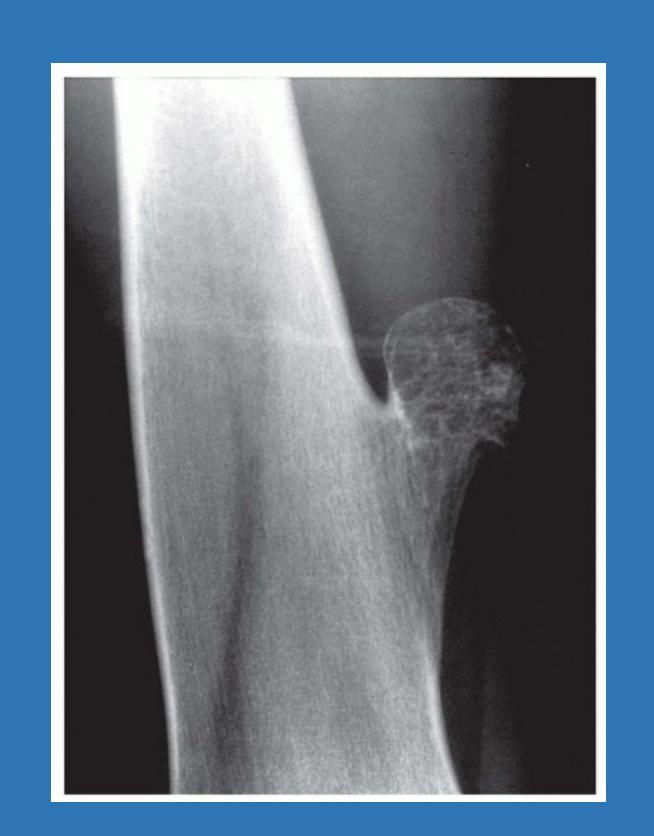

| Compartment Syndrome | Increased pressure within a closed fascial compartment, leading to reduced tissue perfusion, hypoxia, and irreversible muscle and nerve damage. Causes: Fractures (especially tibia/forearm), severe soft tissue trauma, arterial injury, burns, tight casts/dressings, post-ischemic reperfusion swelling, IV fluid extravasation, and bleeding disorders (e.g., hemophilia). High-Risk Notes: Pain may be absent in altered consciousness, children (monitor analgesia response), polytrauma, sedated/epidural cases, or concomitant nerve damage. Open fractures do not always decompress pressure. Gross/Clinical: -tense, shiny leg swelling with blisters in compartment syndrome.Imaging: - Intraoperative fasciotomy | History/Symptoms: Pain out of proportion to the injury (e.g., a “bursting” sensation), which is not relieved by analgesia. Clinical Features (The 5 P’s): - Pain with passive stretch (early, key sign; e.g., ankle dorsiflexion for leg, wrist for forearm). - Paresthesia (early). - Palpable tense swelling (shiny skin, blisters: clear=mild, serosanguinous=severe, bloody=worst; dusky/pallor skin). - Pallor, Paralysis, Pulselessness (late, ominous signs; pulses often palpable until late). Investigations: Primarily a clinical diagnosis (high suspicion key). Compartment pressure measurement can confirm: absolute pressure >30 mmHg or Delta Pressure (Diastolic BP - Compartment P) ≤ 25 mmHg. | Initial: ABCs, supplemental oxygen. Remove all circumferential dressings, casts (bivalve to skin), and splints. Elevate the limb to heart level (not above; higher reduces inflow). Correct any hypotension. Surgical: Urgent Fasciotomy if no response within 1h or confirmed pressure (prophylactic in high-risk like major osteotomy). Release all compartments/skin with long incisions; debride necrotic muscle via 4C’s (early: pink/red, soft, contracts/bleeds on pinch; late: dark, firm, no response); preserve neurovascular. Wound open (bulky dressing/splint, VAC, or boot-lace gradual closure); repeated inspections x48h; coverage in 3-5 days (skin graft usual; flap if nerves/vessels/bone exposed). | Cellulitis, Deep Vein Thrombosis (DVT), Arterial occlusion, Severe soft tissue injury without compartment syndrome; equivocal cases in polytrauma. | Complications: Volkmann’s ischemic contracture (permanent deformity, weakness, sensory loss, chronic pain). Contraindications (Fasciotomy): Confirmed >48h (irreversible damage, high infection risk from dead tissue); crush injuries with already necrotic muscle. |

| Open Fracture | A fracture with a breach in the overlying skin and soft tissues, creating communication with the external environment. All open fractures are considered contaminated (even small punctures; aka compound fracture). Causes: Can result from high-energy trauma (RTAs, falls, firearms; signs: degloving, crush syndrome, bone loss, segmental) or low-energy trauma. Contamination risk higher with farm/soil injuries, bites, delayed presentation (>12h), fecal/oral/soil/water exposure. Mechanism: Low/high velocity missiles (cavitation >300 m/s); in-out (cleaner) vs. out-in (dirtier). Gross/Clinical: ![]() | History: Mechanism of injury (energy, time, place, type/impact method), consciousness, wound size/bleeding amount, other injuries (often missed), tetanus status. Assessment: ATLS protocol (ABCDE) first (treat patient, not fracture; exclude shock/brain injury, monitor vitals; viscera exam: ribs=lungs/liver/spleen, pelvis=bladder/urethra). Examine wound (look/feel/move carefully post-splint), check distal neurovascular status, compartment syndrome. Photograph/remove gross contamination; cover with saline dressing. Classification (Gustilo-Anderson): - Type I: <1 cm wound, clean, minimal soft tissue. - Type II: >1 cm wound, moderate soft tissue (no stripping). - Type IIIA: Extensive soft tissue damage, but adequate bone coverage. - Type IIIB: Extensive soft tissue loss with periosteal stripping; bone exposed, requires flap coverage. - Type IIIC: Any open fracture with an arterial injury requiring repair. | Initial (ER): ATLS first. Cover wound with sterile saline-soaked dressing, splint limb, IV fluids (request blood if needed); traction if no distal pulse/deformity. Prophylaxis: Tetanus prophylaxis/serum and broad-spectrum IV antibiotics immediately (culture tissue/blood); clean major contamination. Surgical: Urgent debridement/irrigation within 6-12h (“Dilution is the solution to pollution”; pulse-irrigate 3-6-9L saline; excise non-viable tissue/foreign material, trim skin edges, remove dead muscle/detached bone, preserve N/V). Stabilization: external fixator (preferred severe; replace with cast post-infection); internal if clean/minimal. Wound closure delayed (primary if small/clean; secondary if contaminated/large). Early soft tissue cover. | The diagnosis is typically obvious. Key: Classify severity; identify associated injuries like compartment syndrome, vascular damage, or high-energy signs (e.g., crush). Differentials for contamination: Primary (field debris) vs. secondary (post-fixation if poor debridement). | Complications: Infection (cellulitis, osteomyelitis, chronic with sequestra/drainage, gas gangrene), tetanus; higher with delay/exposure/bites. - embolisms fat, thrombi others.. Case Insight: Unconscious patient (e.g., open tibia post-RTA): ABCDE/cervical collar, distal pulses/traction, admit for debridement; ankle fall: Splint post-ABC, assess neurovascular. |